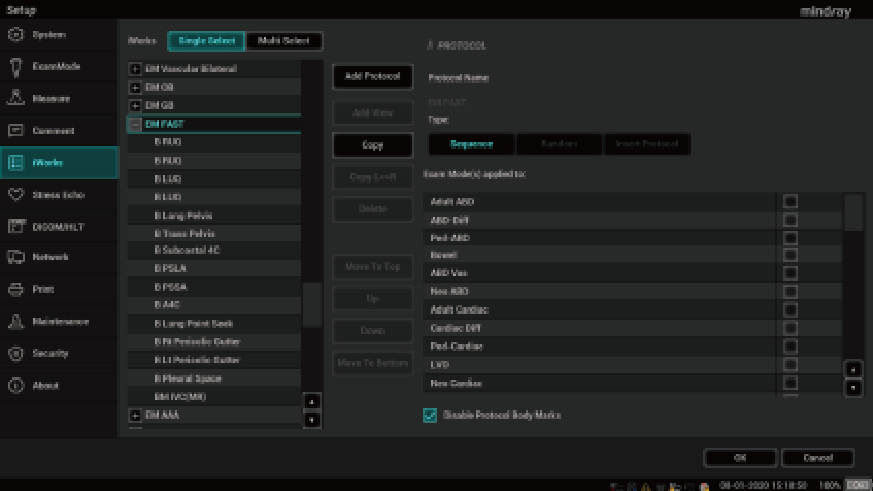

Des outils intelligents pour la gestion des fluides

1Smart B-line

Le Smart B-line calcule automatiquement le nombre de lignes B et le pourcentage de zones de lignes B en accord avec le protocole sÃĐlectionnÃĐ pour une ÃĐvaluation rapide du tissu pulmonaire. Un schÃĐma global des poumons et un codage couleur du score pulmonaire permettent une ÃĐvaluation simple de la fonction pulmonaire.

2Smart VTI (ITV)

Mesure automatique de lâintÃĐgrale temps Vitesse (ITV) et du dÃĐbit cardiaque pour permettre une ÃĐvaluation rapide de la fonction cardiaque. Lâoutil place automatiquement la boite couleur et la ligne de tir du doppler pulsÃĐ en temps rÃĐel. Un graphique de tendances reprÃĐsentant le dÃĐbit cardiaque, le volume dâÃĐjection systolique et lâITV aide à la prise de dÃĐcision.

3Smart IVC

Mesure automatique de la Veine Cave InfÃĐrieure (VCI) pour aider à lâÃĐvaluation de la volÃĐmie et guider la gestion des fluides. Un graphique de tendances reprÃĐsentant lâindex de collapsibilitÃĐ ou lâindex de distensibilitÃĐ et la variation de la veine cave infÃĐrieure permet le suivi de lâÃĐvolution des patients en ÃĐtat critique.